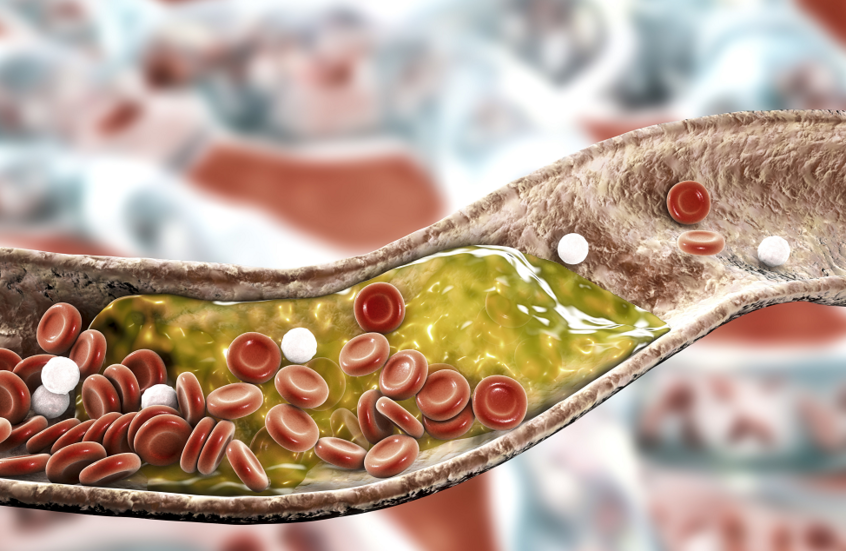

اكتشاف وسيلة للإنقاذ من مرض رئوي مميت

تمكن علماء جامعة فاندربيلت الأمريكية من ابتكار طريقة لتجديد الرئات المزروعة، التي ستساعد على إنقاذ حياة المرضى الذين يعانون من أمراض الجهاز التنفسي في مرحلتها النهائية.

ويفيد موقع MedicalXpress بأن الباحثين استخدموا تقنية الدورة الدموية المتقاطعة في الخنازير التي يمكن أن تدعم عمل الرئتين مدة 36 ساعة متتالية. هذه الفترة الزمنية تسمح للأطباء بإجراء عمليات إضافية مكرسة لإصلاح الأنسجة لعملية الزرع اللاحقة.

موزع سجائر يقيم دعوى ضد مشغليه بعد إصابته بسرطان الرئة

كما تسمح هذه الطريقة بتحسين حالة الرئتين المتضررة نتيجة اشتفاف (تهوية) محتويات المعدة والمجاري التنفسية. سابقا كان على الأطباء خلال ست ساعات تحديد صلاحية الرئتين للزرع، وهذا الوقت غير كاف للقيام بجميع عمليات الإصلاح. يخطط الباحثون إلى توسيع هذه الفترة (36 ساعة) إلى أيام وحتى أسابيع.